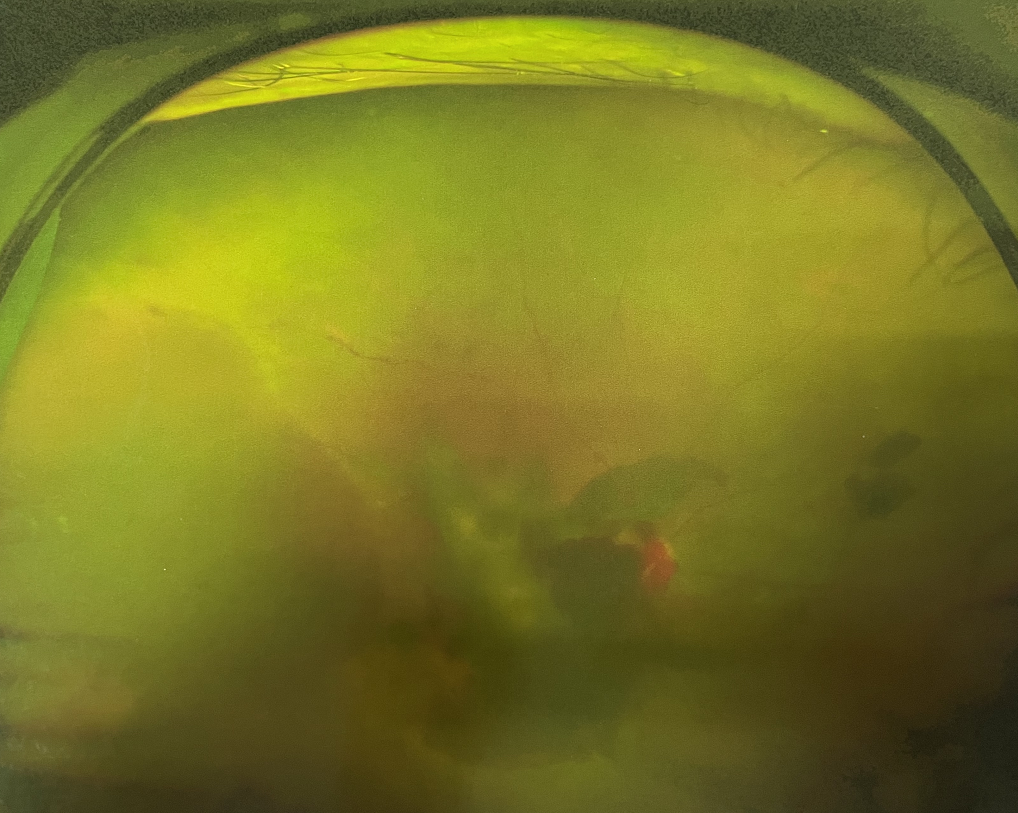

眼底出血不是獨(dú)立的眼病,而是由于眼球自己的病變和某些全身疾病的并發(fā)癥導(dǎo)致眼底的視網(wǎng)膜或脈絡(luò)膜出血,如果出血量大就會(huì)進(jìn)入到眼球的玻璃體內(nèi),從而影響視力,如果沒有得到恰當(dāng)?shù)闹委熆蓭?lái)更嚴(yán)重的并發(fā)癥造成失明。

眼底出血的患者,如果出血量少,而且在視網(wǎng)膜周邊部可能沒有明顯癥狀,患者僅感到眼前有黑影浮動(dòng);如出血量多,將嚴(yán)重影響視力,甚至完全被黑影所遮擋僅剩光感;如出血位于視網(wǎng)膜的黃斑區(qū),患者視野中心區(qū)被暗影遮擋,周邊尚有部分視力。

先是散瞳檢查眼底,可以明確眼底出血的性質(zhì),出血部位和出血量有多少。眼B超檢查,對(duì)于眼底出血量特別多,無(wú)法看清眼底的患者,就需要進(jìn)行眼部B超檢查,以了解出血量,出血部位、有無(wú)合并視網(wǎng)膜脫離;還可以明確是否患有視網(wǎng)膜或脈絡(luò)膜的腫瘤。